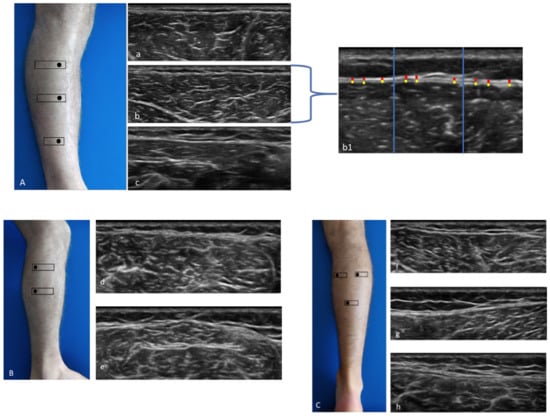

1. Anterior region (Figure 1A): Patient relaxed in supine position with right lower limb in neutral position.

Anterior 1 (Ant 1): below the tibial crest, anterior proximal third of the leg (Figure 1A(a)).

Anterior 2 (Ant 2): the probe was moved downwards following the anterior tibialis muscle at level of the anterior middle third of the leg, moving the probe laterally until the muscle belly of the anterior tibialis muscle is centered in the monitor (Figure 1A(b)).

Anterior 3 (Ant 3): the probe was moved downwards, and the image was evaluated at the point before of the superior retinaculum of the flexors (Figure 1A(c)).

2. Lateral region (Figure 1B): Patient in left lateral decubitus to assess right limb and vice versa.

Lateral 1 (Lat 1): the probe was placed transversally to the lateral proximal third of the leg, taking the peroneal head as landmark, above the peroneal longus muscle (Figure 1B(d)).

Lateral 2 (Lat 2): the probe was moved downwards following the peroneal bone until visualization of the peroneal longus muscle with the peroneal brevis muscle underneath (Figure 1B(e)).

3. Posterior region (Figure 1C): Patient prone with lower limb in neutral position.

Posterior 1 (Post 1): the probe was placed axially at the level of medial belly of gastrocnemius muscle under the popliteal fold, maintaining the sural nerve at the center of the image (Figure 1C(f)).

Posterior 2 (Post 2): the probe was moved laterally until the level of lateral belly of gastrocnemius muscle (Figure 1C(g)).

Posterior 3 (Post 3): the probe was moved downwards until that following as landmark the visualization of the sural nerve and the sural vein, visualizing the two bellies of the gastrocnemius muscle and the soleus muscle (Figure 1C(h)).

All measurements for the epimysial fascia were performed only at anterior 2 level, because it was the only area where was possible to the distinction between deep fascia and epimysial fascia of the tibialis anterior muscle.

The images for each region/level were frozen and captured at the end of each assessment, and fascial thickness was measured by Image J analysis software. Each image was divided into three regions; in each of them, three points representing the best visibility were measured and averaged (Figure 1A(b1)). To eliminate the influence of possible thickness variations, three equidistant points per image were measured and the resulting values were averaged for analysis. The scanner settings were kept constant during the study [37].

Figure 1. Ultrasound (US) images of the anterior (A), lateral (B), and posterior (C) compartments. Anterior compartment (A) at the levels Ant 1 (a), Ant 2 (b), and Ant 3 (c); method of measurement (b1). Lateral compartment (B) at levels Lat 1 (d) and Lat 2 (e). Posterior compartment (C) at the levels Post 1 (f), Post 2 (g), and Post 3 (h). Probe: black rectangle. Yellow dashes: epimysial fascia; red dashes: crural fascia.